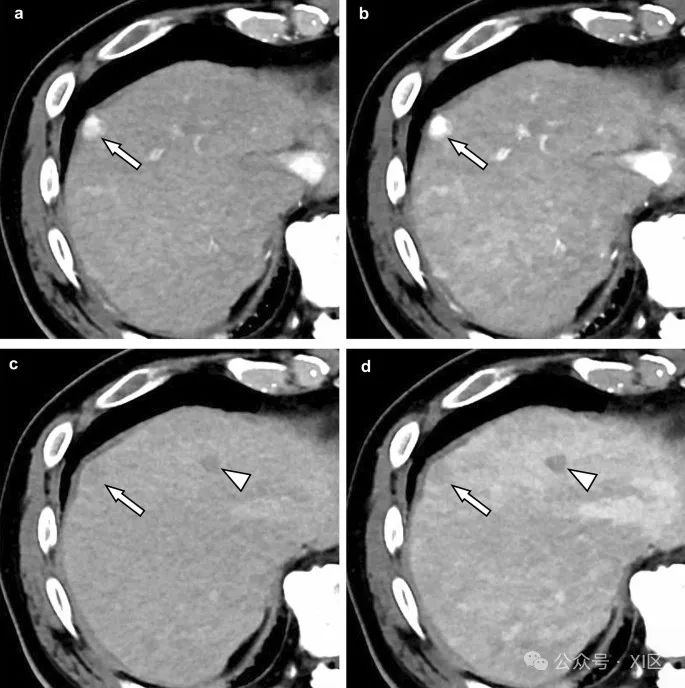

图5 动脉期(A, B)和平衡期(C, D)在70 keV(A, C)和50 keV(B, D)的增强光子计数CT图像。动脉增强和HCC的洗脱模式在50 keV图像(B, D)上比在70 keV图像(A, C)上更清晰地可见(箭头)。低血管结节(箭头:疑似发育不良结节)在50 keV图像(B)上的轮廓也比在70 keV图像(D)上更清晰。肝转移